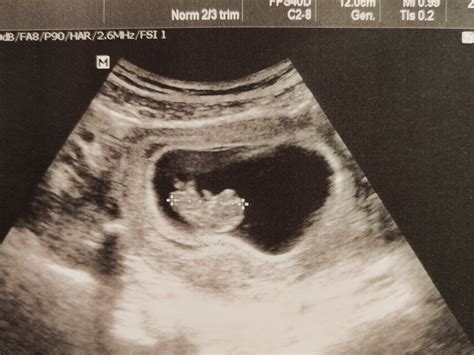

20. týždeň tehotenstva - morfologický ultrazvuk v 2. trimestri

Od 20. týždňa tehotenstva už veľkosťou bábätko pripomína žltý melón alebo grapefruit. Samozrejme, len rozmermi, štruktúrou už ide o malého človiečika. CRL plodu sa pohybuje okolo 16 - 17 cm. Celková dĺžka tela, ktorá sa od 20. tt sleduje prioritne, je približne 25 - 27 cm a hmotnosť plodu je asi 300 až 340 g.

Všetky tieto parametre vám môže odhaliť v 20. týždni tehotenstva ultrazvuk, tzv. ultrazvukový skríning v druhom trimestri, veľký ultrazvuk alebo tiež morfologický ultrazvuk. Vykonáva sa medzi 18. - 22. týždňom. Väčšina lekárov termín tohto vyšetrenia dáva na 21. - 22. týždeň z dôvodu zrelosti bábätka. Druhý veľký ultrazvuk je v tehotenstve považovaný za najdôležitejší.

Lekár počas ultrazvuku detailne sleduje celkový vývoj bábätka, a to od vývinu orgánov - srdce, mozog, obličky, pľúca, žalúdok až po samotné tvary hlavičky, prstov, končatín a podobne. Sleduje takisto genitálie plodu, ktoré by pri správnej polohe mali byť dobre rozoznateľné. Dôležité je monitorovať aj polohu plodu v 20. tt v prípade komplikácií. Sleduje sa množstvo plodovej vody či lokácia placenty. Počas ultrazvuku je dôležité sledovať hlavne chromozomálne odchýlky a výskyt prípadných porúch - Downov syndróm, Edwardsov syndróm a pod. Podobne sa sledujú aj deformácie alebo vývojové poruchy - tvar hlavy, veľkosť mozgu, poloha nosu, chyby chrbtice alebo vstup pupočníka do bruška a podobne.

Ultrazvukové vyšetrenie v tehotenstve trvá približne 10 až 30 minút - závisí od toho, či ide o bežný kontrolný malý ultrazvuk, ktorý lekár robí na každej tehotenskej poradni (môže trvať niekedy 3 až 5 minút), alebo je to „veľký“ ultrazvuk napríklad v 20. týždni.